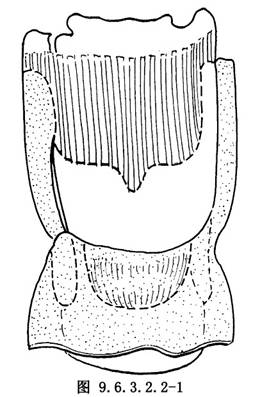

10.4 4.暴露甲狀軟骨分離外骨衣

頸前帶狀肌切斷後,暴露甲狀軟骨,在甲狀軟骨上緣水平切開外骨衣,用小剝離子向下剝離外骨衣至甲狀軟骨下緣(圖9.6.3.2.2-1)。